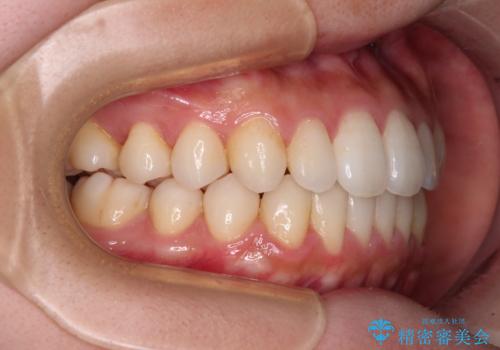

インビザラインで口を閉じやすく

- 下唇に上の前歯が当たることを気にして来院された患者様です。

上顎の親知らずを抜去し、歯列全体を後方に移動させるとともに、IPR(歯と歯の間を削る)を行うことで口元の閉じにくさを改善していくこととしました。

咬合力が強く、マウスピースを介した咬み込みが顕著であったため、奥歯の咬みにくさやIPRのスペースが改善しにくく、治療期間が思った以上にかかってしまいました。